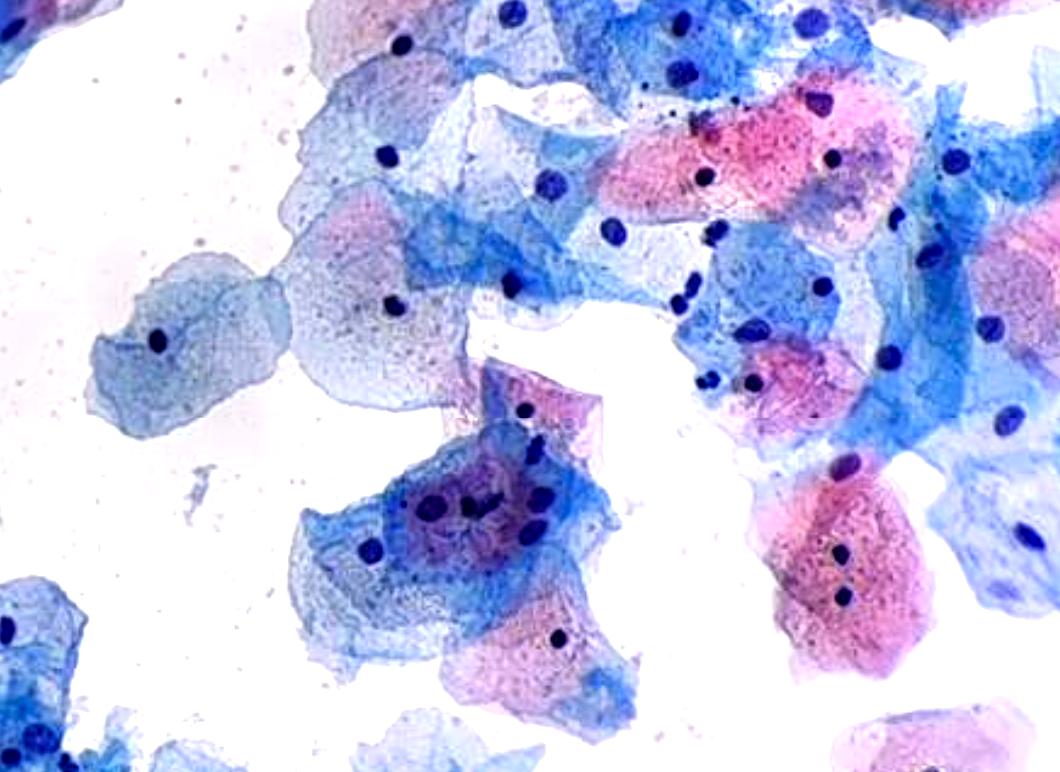

Pap Smear

AI-assisted cervical cancer screening with Bethesda classification system integration (beta version)